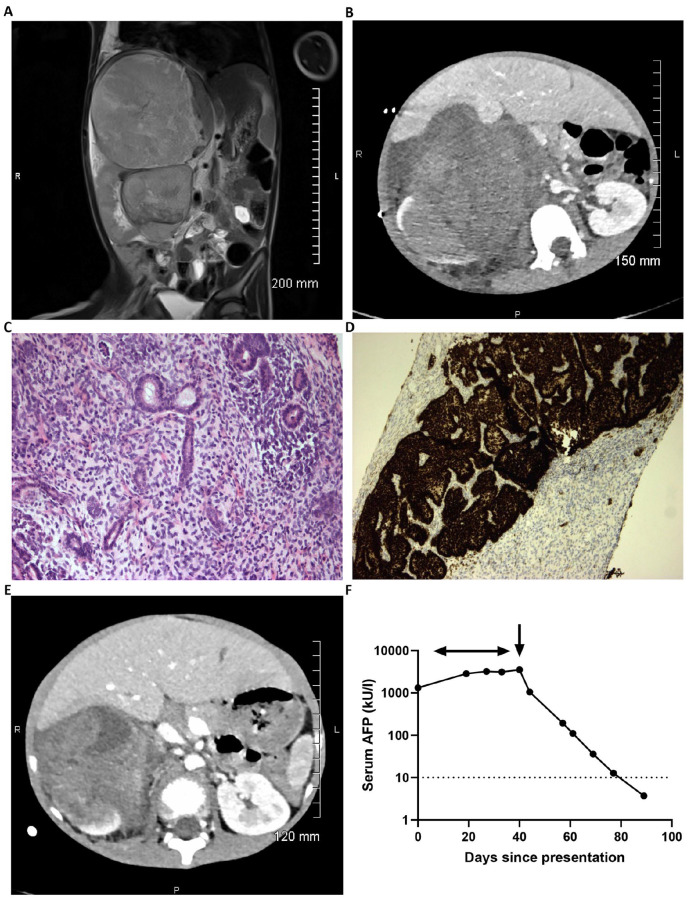

Wilms tumor (WT) is the commonest cause of renal cancer in children. In Europe, a diagnosis is made for most cases on typical clinical and radiological findings, prior to pre-operative chemotherapy. Here, we describe a case of a young boy presenting with a large abdominal tumor, associated with raised serum alpha-fetoprotein (AFP) levels at diagnosis. Given the atypical features present, a biopsy was taken, and histology was consistent with WT, showing triphasic WT, with epithelial, stromal, and blastemal elements present, and positive WT1 and CD56 immunohistochemical staining. During pre-operative chemotherapy, serial serum AFP measurements showed further increases, despite a radiological response, before a subsequent fall to normal following nephrectomy. The resection specimen was comprised of ~55% and ~45% stromal and epithelial elements, respectively, with no anaplasia, but immunohistochemistry using AFP staining revealed positive mucinous intestinal epithelium, consistent with the serum AFP observations. The lack of correlation between tumor response and serum AFP levels in this case highlights a more general clinical unmet need to identify WT-specific circulating tumor markers.